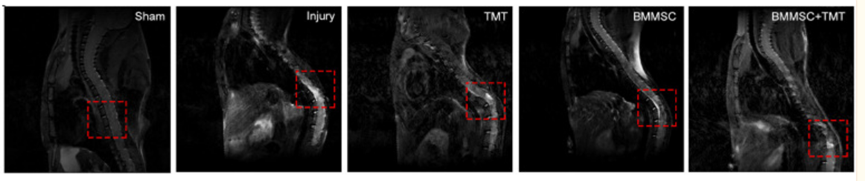

有研究表示,间充质干细胞移植可以有效减轻脊髓损伤的程度,有利于机体的恢复。Sun等人研究发现,当使用8周的间充质干细胞治疗之后,同样病患的脊髓损伤程度比不接受干细胞疗法的病患要轻得多。

(图片来自参考文献4)